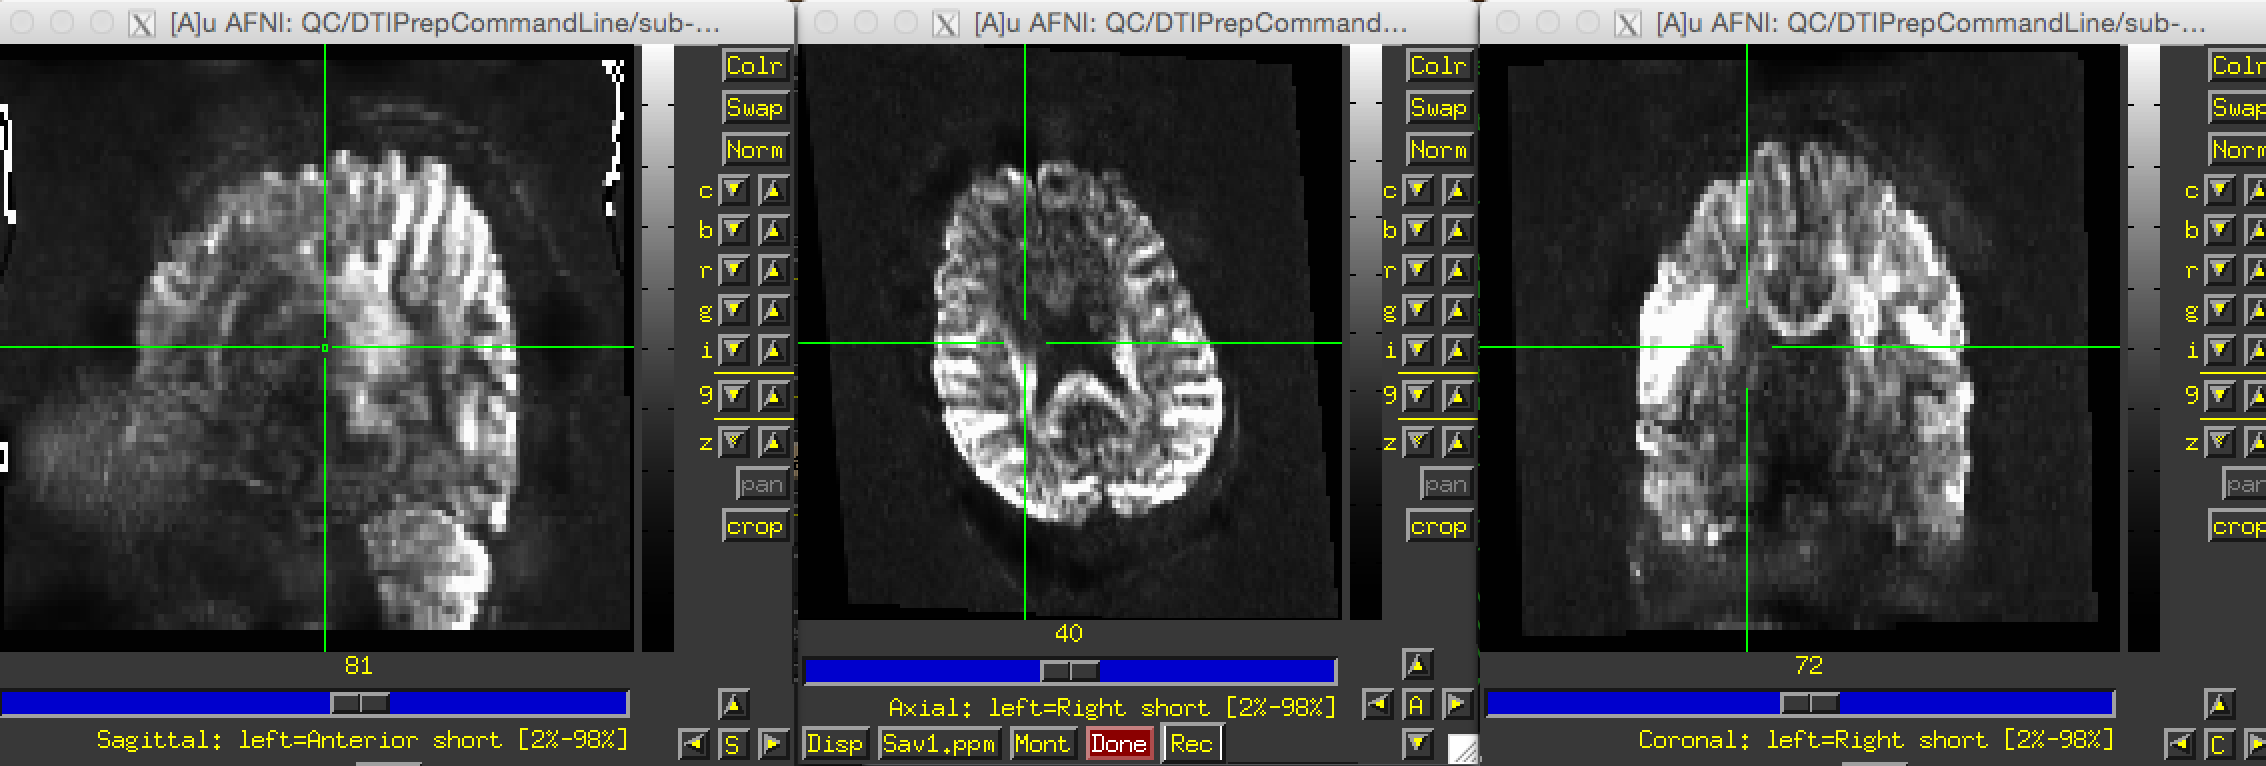

I have a multi-band DTI dataset(MB factor 3) which visually appears to be fine and when I use FSL to compute the motion params, it gives me mean motion of 1.3 and max of 2.9. Ideally, this data set should pass the QC. But when I use DTIPrep to process, the output QCed image has only 8 dirs left out of 137 and the dataset does not pass the QC. Please find attached the screenshot of one of the directions of the QCed image. The image looks distorted too.

Not sure about the distortions, to me it looks like that the voxelsize information in the volume may be incorrect as it seems stretched in inferior-superior direction (or at least incorrect the way AFNI displays it, does it look similarly in fsl if you use fslview, or in Slicer?). It is possible that your acquisition uses a slice overlap and thus that the voxelsize in the slice-direction has been set to the DICOM slice thickness instead of the slice step (difference in slice-position between slices).